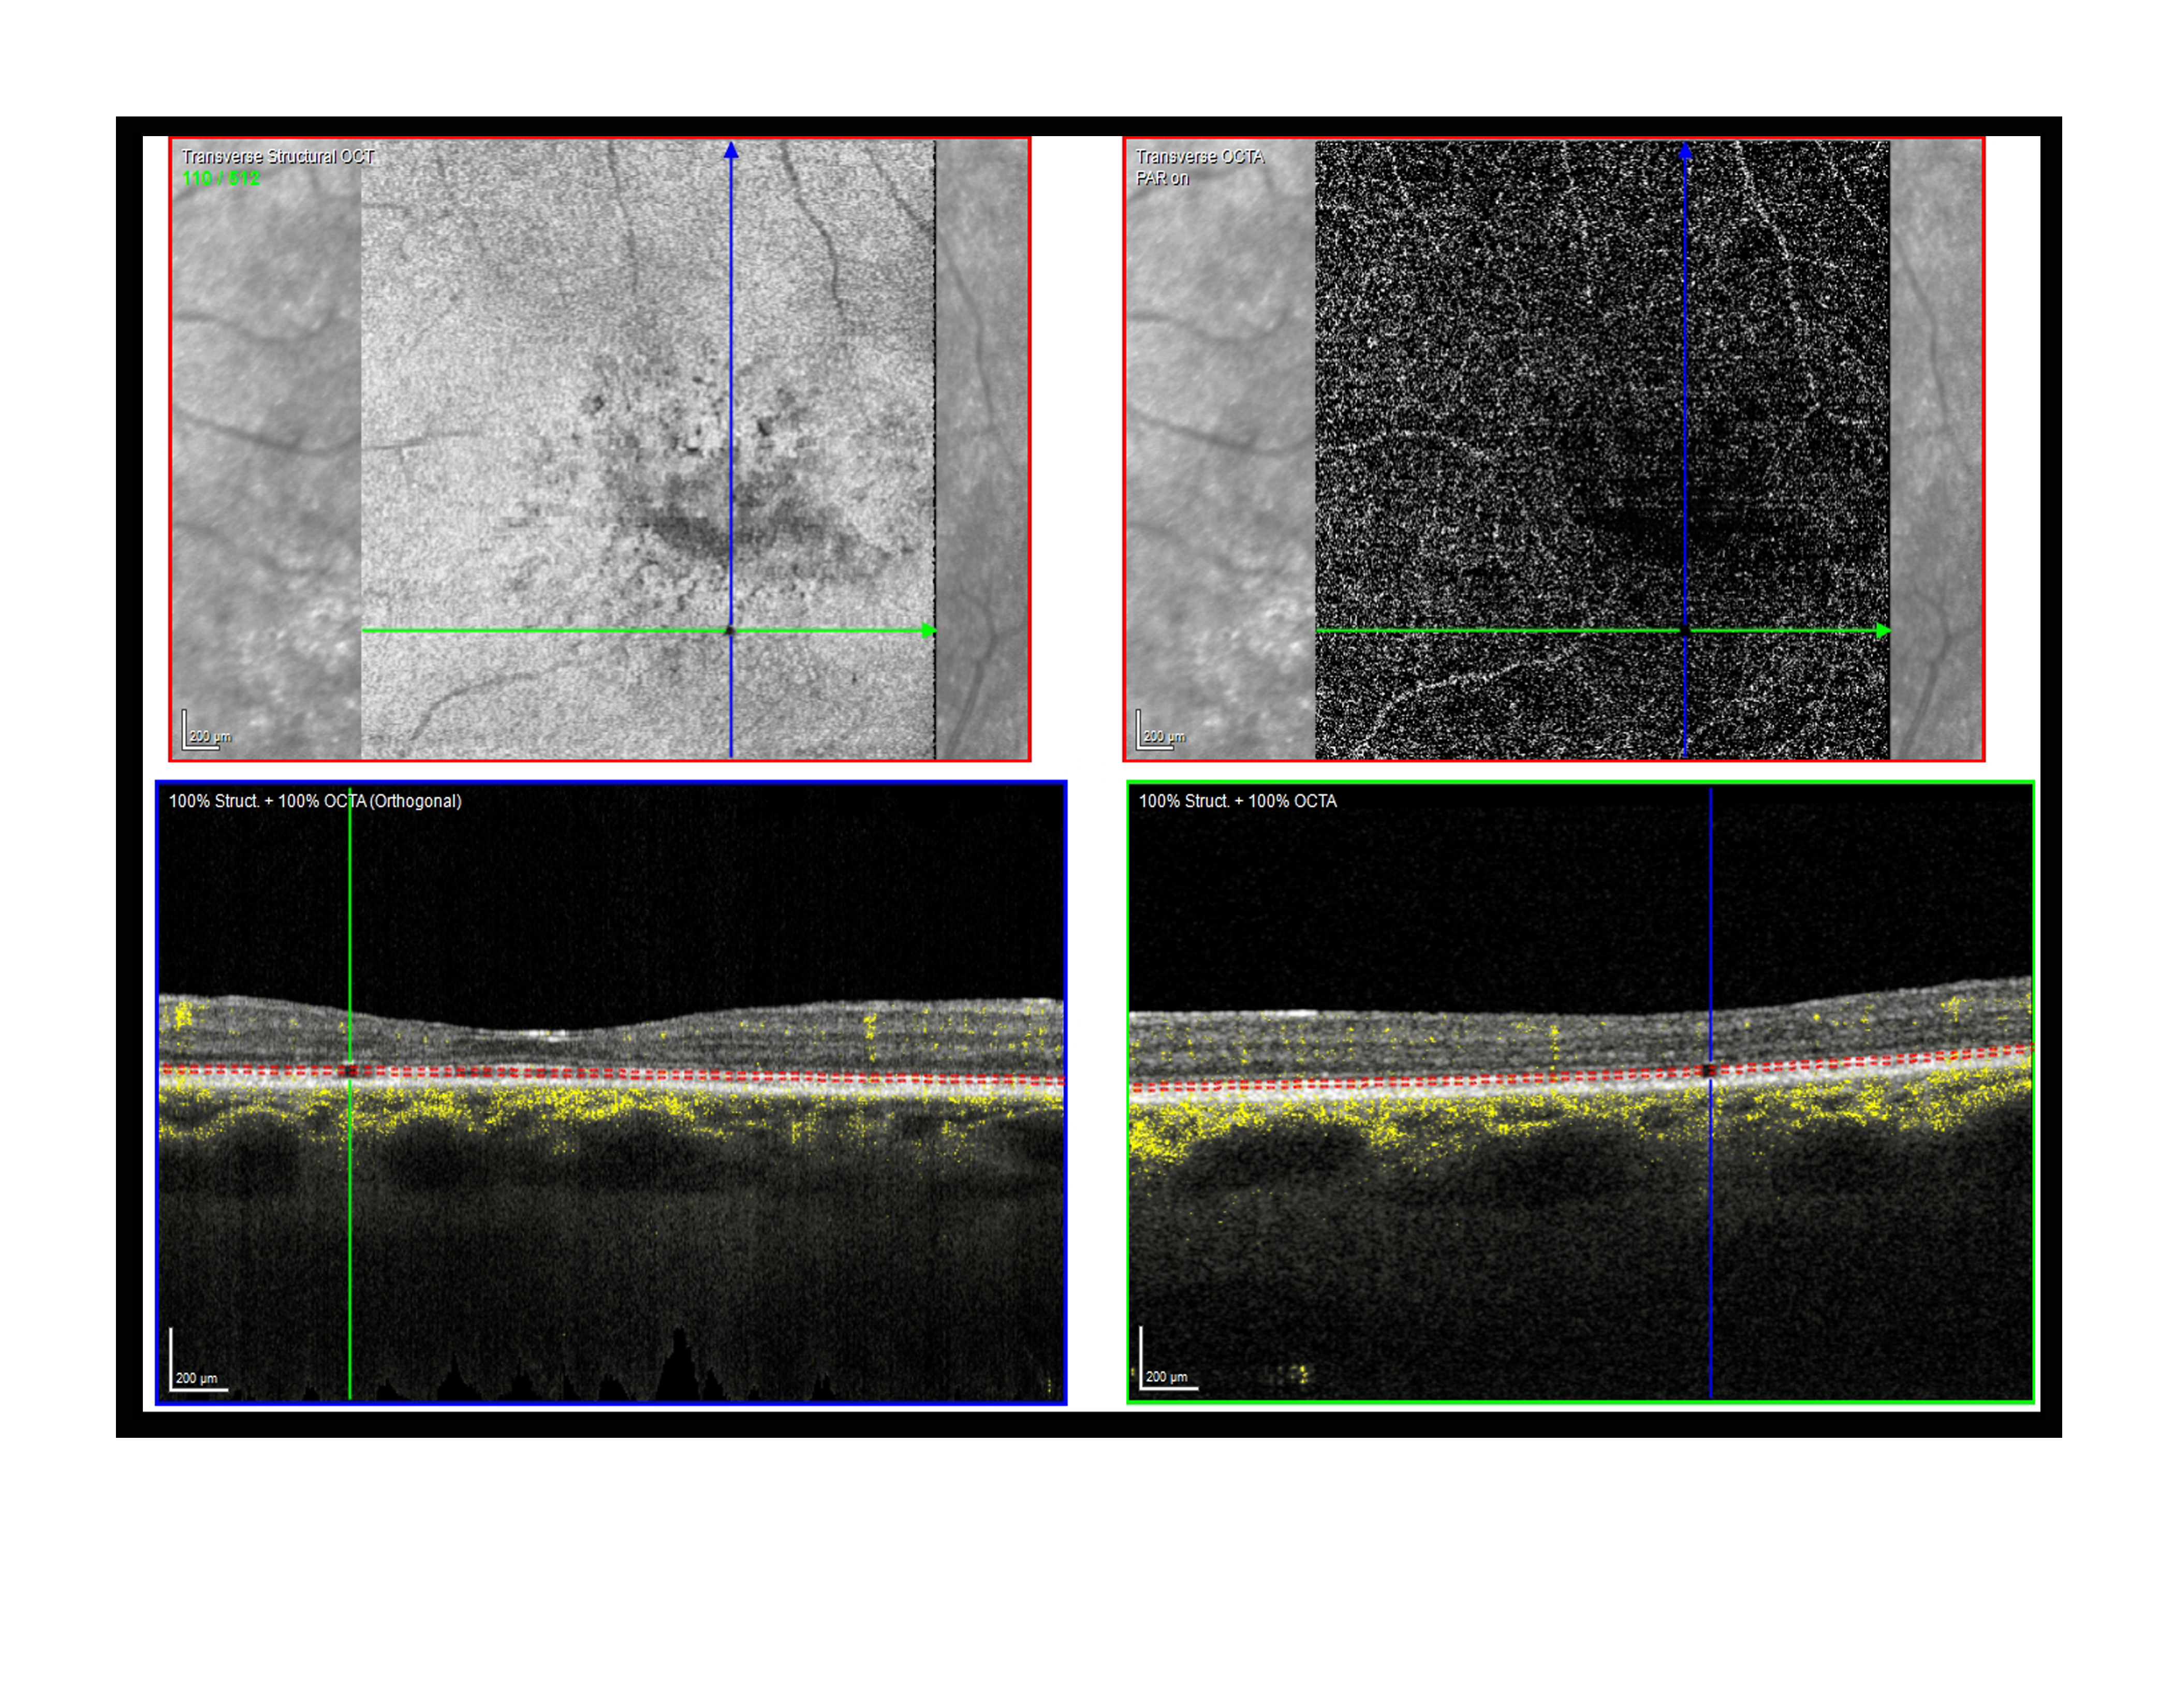

RPE Voids Presented by Paul Crown, CRA, OCT-C This photograph received Second Place in the category "Optical Coherence Tomography Angiography" and was displayed in the 2024 OPS Exhibit. Filed Under Retina OPS Photo